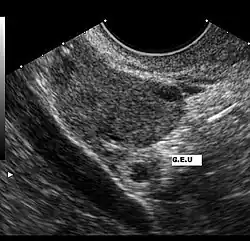

Ultraschallbild einer Extrauteringravidität

Eine Extrauteringravidität muss bei jeder Frau mit Bauchschmerzen oder vaginaler Blutung bei positivem Schwangerschaftstest angenommen werden. Eine Ultraschalluntersuchung, die außerhalb der Gebärmutter einen Fruchtsack mit fetalen Anteilen und Herzaktionen zeigt, ist beweisend für eine Extrauteringravidität.

Ein zu geringer Anstieg des β-hCG im Serum kann ebenfalls ein Hinweis auf eine ektope Schwangerschaft sein. Ab einem β-hCG-Wert von etwa 1500 IU/ml ist eine normale intrauterine Schwangerschaft im Ultraschall mit hoher Wahrscheinlichkeit darstellbar. Zeigt eine hochauflösende transvaginale Sonografie bei einem solchen Wert keine intrauterine Schwangerschaft, muss eine Extrauteringravidität in Betracht gezogen werden.